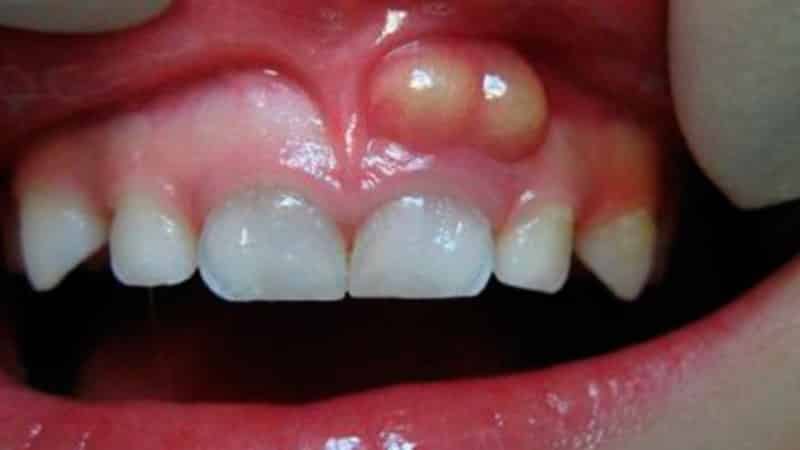

Кроме того, у вашего малыша могут быть и другие причины, вызывающие беспокойство. Обратите внимание на фотографии опухших десен у детей.

Часто у малышей диагностируют флюс, который приводит к отечности или образованию свища над воспаленным участком. Это происходит из-за запущенного кариеса. Если дело доходит до периодонтита, коренной зуб может серьезно пострадать. Поэтому важно своевременно лечить все заболевания полости рта.